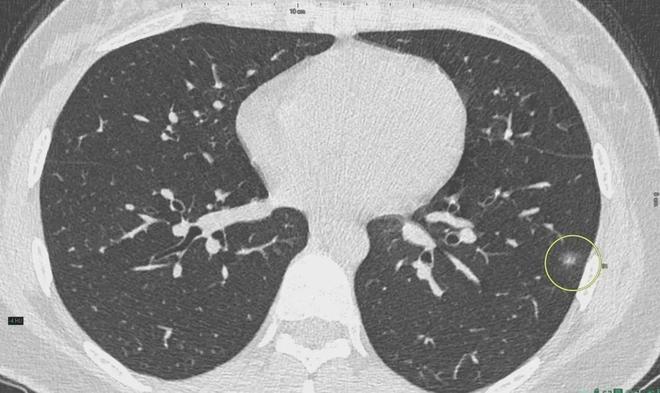

肺結(jié)節(jié)是一種常見的肺部疾病,其發(fā)病率逐年上升,雖然肺結(jié)節(jié)多數(shù)情況下是良性的,但也有可能惡化為肺癌,了解肺結(jié)節(jié)的形成原因?qū)τ陬A(yù)防和治療具有重要意義,本文將為您詳細(xì)解析肺結(jié)節(jié)的形成機制。